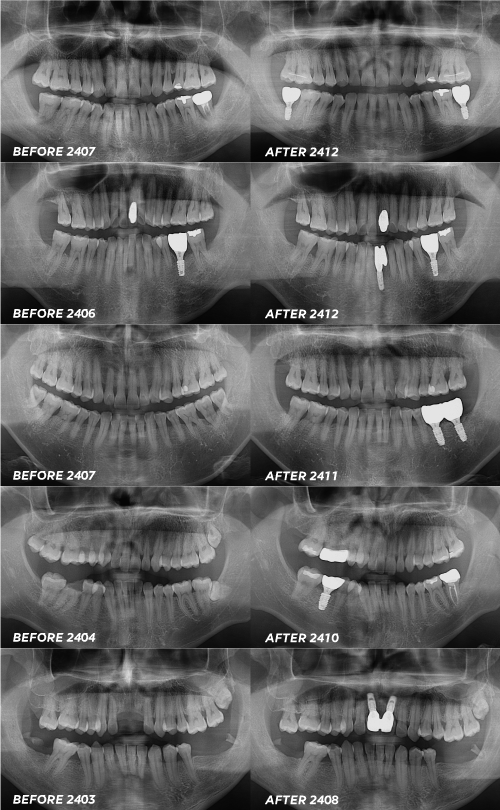

서울센텀치과 소량 부위 임플란트 사례